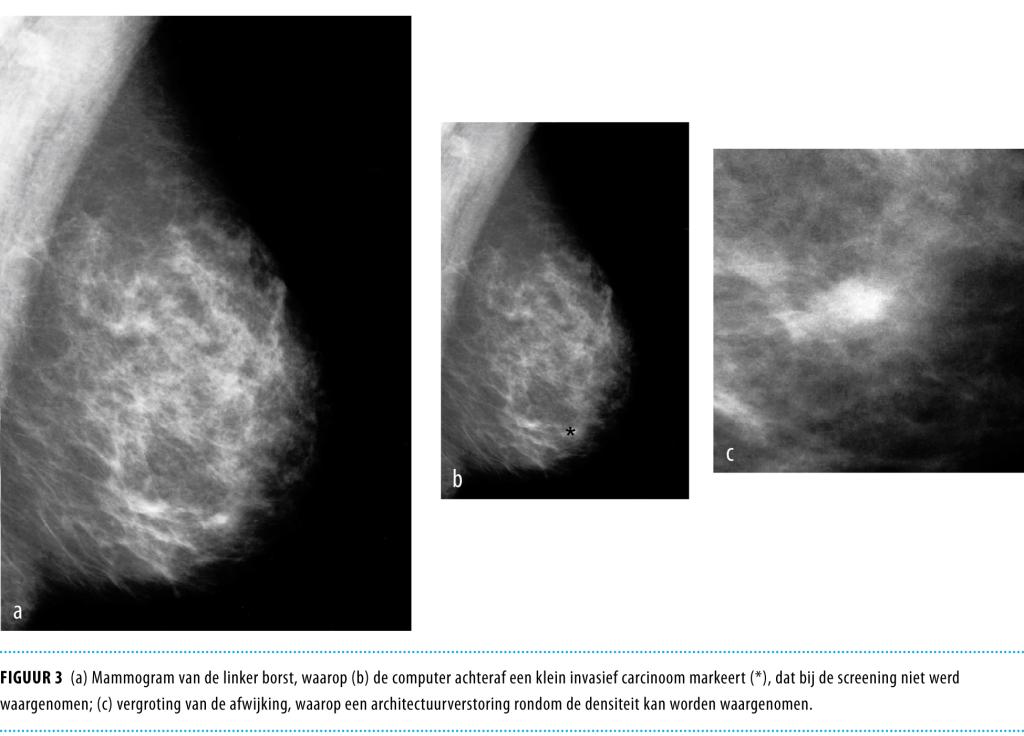

• Als alternatief kan de computer worden ingezet om afwijkingen op te sporen. Computerondersteunde detectie (CAD) wordt in sommige landen al op grote schaal toegepast. Het ligt in de rede om CAD naast de huidige dubbele beoordeling in te zetten.